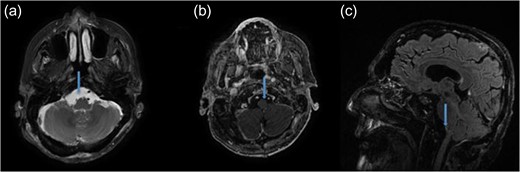

The patient underwent microsurgical resection via far-lateral transcondylar approach in park bench position (Fig. 2a). The tumor was tan-colored and extremely firm, extending inferiorly to the entrance of the vertebral artery. It also extended into the hypoglossal canal and jugular foramen (Fig. 2b). The PICA, which was initially encased by tumor, and cranial nerve IX, X and XI were all preserved (Fig. 2c). Gross total resection was achieved (Fig. 2d). No changes of motor evoked potentials were observed throughout the surgery. The postoperative course was uneventful and images confirmed gross total resection (Fig. 3, video 1). Histopathological examination of the tumor revealed prostate adenocarcinoma metastasis positive for prostatic specific antigen. There was focal necrosis and a high proliferative index assessed by Ki 67.

Intraoperative images showing (a) the T that was extrinsic to the cerebellum and medulla oblongata (MO), was pushing CN XI medially and encasing dentate ligament (DL). (b) CN XII encased by T. (c) PICA and Vertebral Artery (VA) encased by T. (d) After tumor resecting cranial nerve VII, VIII (CN VII, VIII), anterior inferior cerebellar artery (AICA) and CN IX, X, XI preserved.